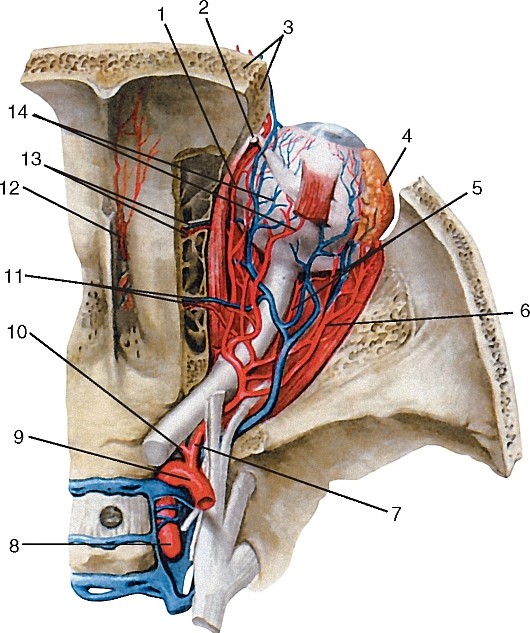

Анатомия внутренней яремной вены: КТ изображения